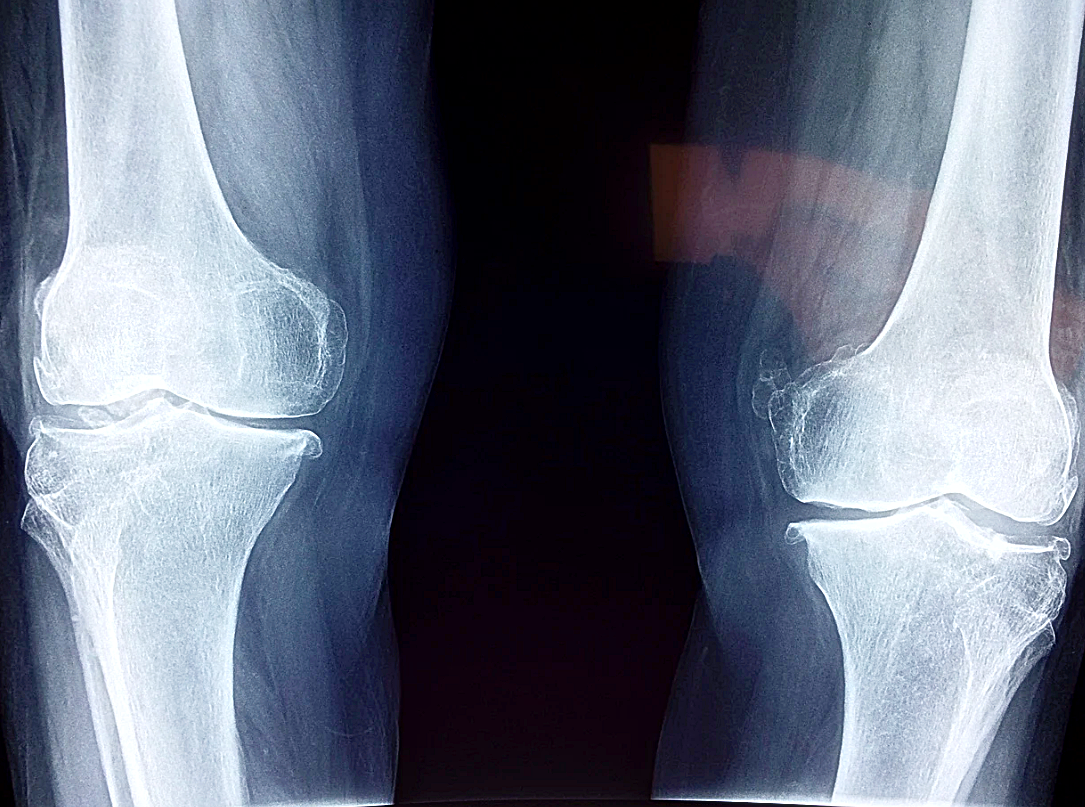

비타민 D의 부족하게 되면

혈중 칼슘, 인의 농도가 낮아져

골격이 약화되어 골다공증, 골연화증 등이

발생할 가능성이 높아지게 되고

뼈 건강

비타민 d에는 파골세포와 조골세포를

조절하는 오스테오칼신 성분과 오스테오폰틴

성분이 함유되어 있는데요 오스테오칼신 성분은

칼슘과 인의 농도를 조절하고 오스테오폰틴 성분은

파괴되는 뼈의 골격 위치를 재구성하는 기능을

담당하고 있습니다. 때문에 비타민 d를 꾸준히

섭취하시면 뼈를 튼튼하게 유지하는데 도움이 됩니다.